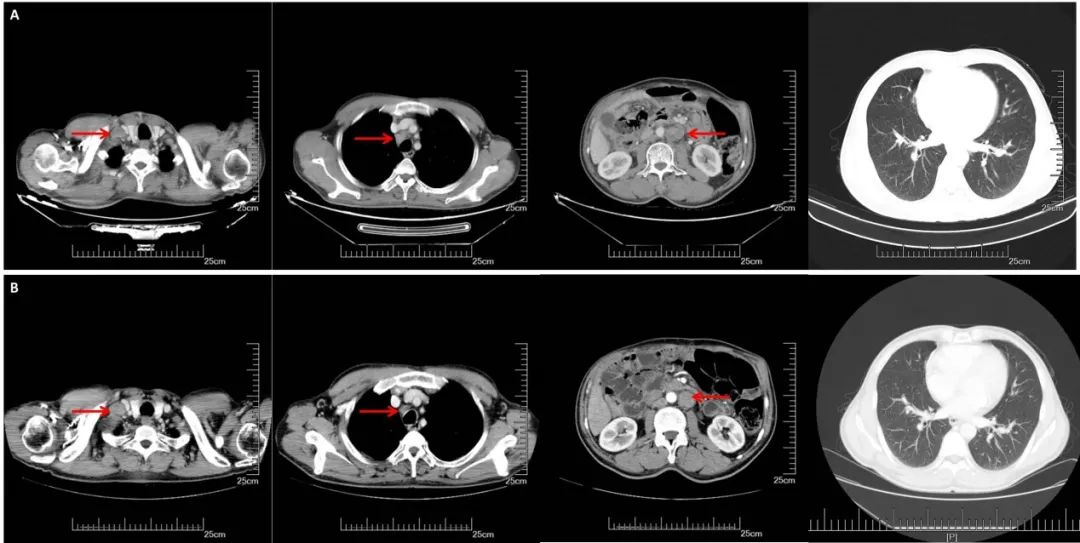

A:CT增强(2016.08.22): 胃体小弯侧增厚,肝胃间、腹膜后多发淋巴结转移,双肺多发转移。B:2周期化疗后CT增强(2016.10.19):胃壁增厚减轻,淋巴结明显缩小,双肺多发转移灶几乎消失

A:CT增强(2017.09.29):右锁骨上,纵膈,腹腔淋巴结明显增大,双肺无明显变化;B:CT增强(2018.03.27):腹膜后多发增大淋巴结较前缩小,右侧锁骨上纵隔内见多发淋巴结,部分较前增大,双肺较前变化不大。